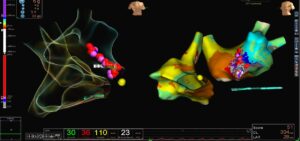

3D LAT Activation Mapping: Identifying the Circuit

LAT activation mapping demonstrated a macro re-entrant circuit in the left atrium.

Propagation mapping showed wavefront circulation consistent with atypical LA flutter

In post-CABG patients, surgical scarring and atrial remodeling often create slow-conduction channels. These channels act as substrates for re-entry.

The propagation map clearly visualized wavefront movement around a scar region, confirming the arrhythmia was left atrial in origin rather than typical right atrial cavotricuspid isthmus flutter.

Ablation Strategy: Correlation with ILAM and Voltage Map

The critical isthmus was identified along the anterior mitral region.

As shown on, the linear lesion connected anatomical landmarks to interrupt the re-entry circuit permanently.